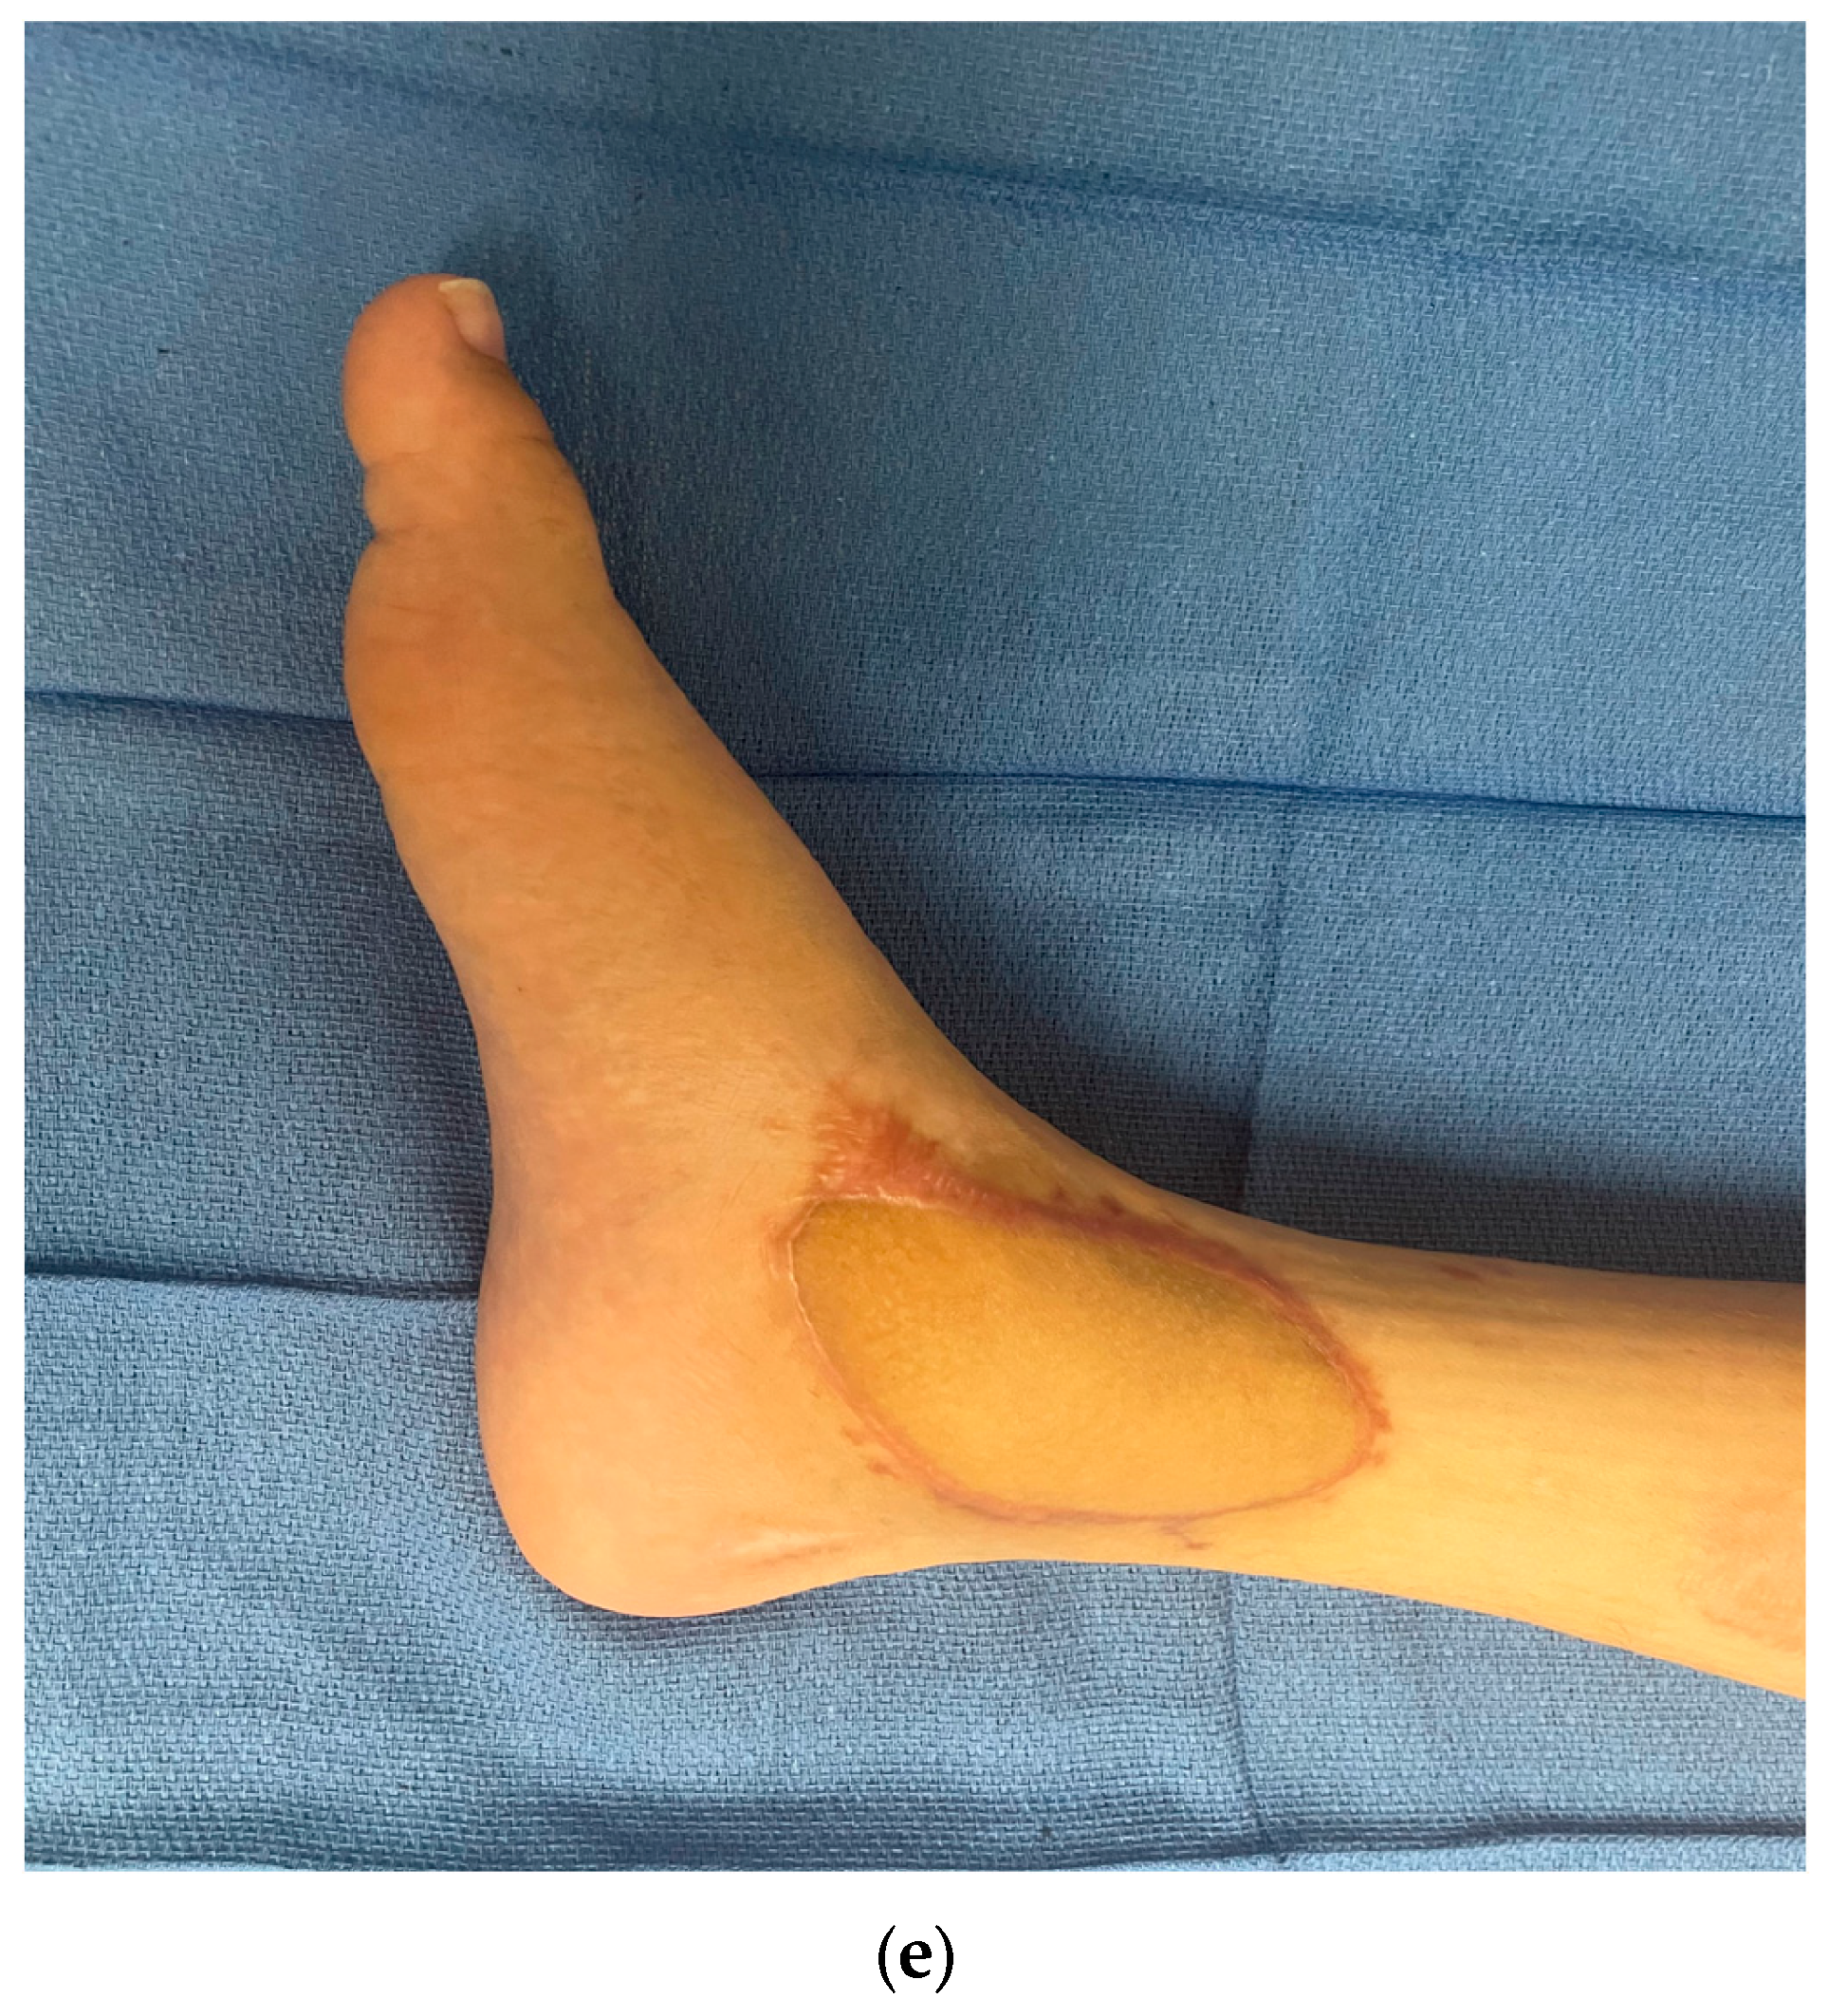

3.3. Postoperative Monitoring

- Long, E.; Maselli, A.; Barron, S.; Morgenstern, M.; Comer, C.D.; Chow, K.; Cauley, R.; Lee, B.T. Applications of Ultrasound in the Postoperative Period: A Review. J. Reconstr. Microsurg. 2022, 38, 245–253. [Google Scholar] [CrossRef] [PubMed]

- Gonzalez, J.; Gardikiotis, I.; Ruiz-Moya, A.; Fontdevila, J.; Weshahy, O.; Palacin, J.; Vinals, J.; Hong, J.P. Duplex echography as an adjuvant tool to clinical examination to detect early postoperative free flap vascular compromise. Microsurgery 2021, 41, 109–118. [Google Scholar] [CrossRef]